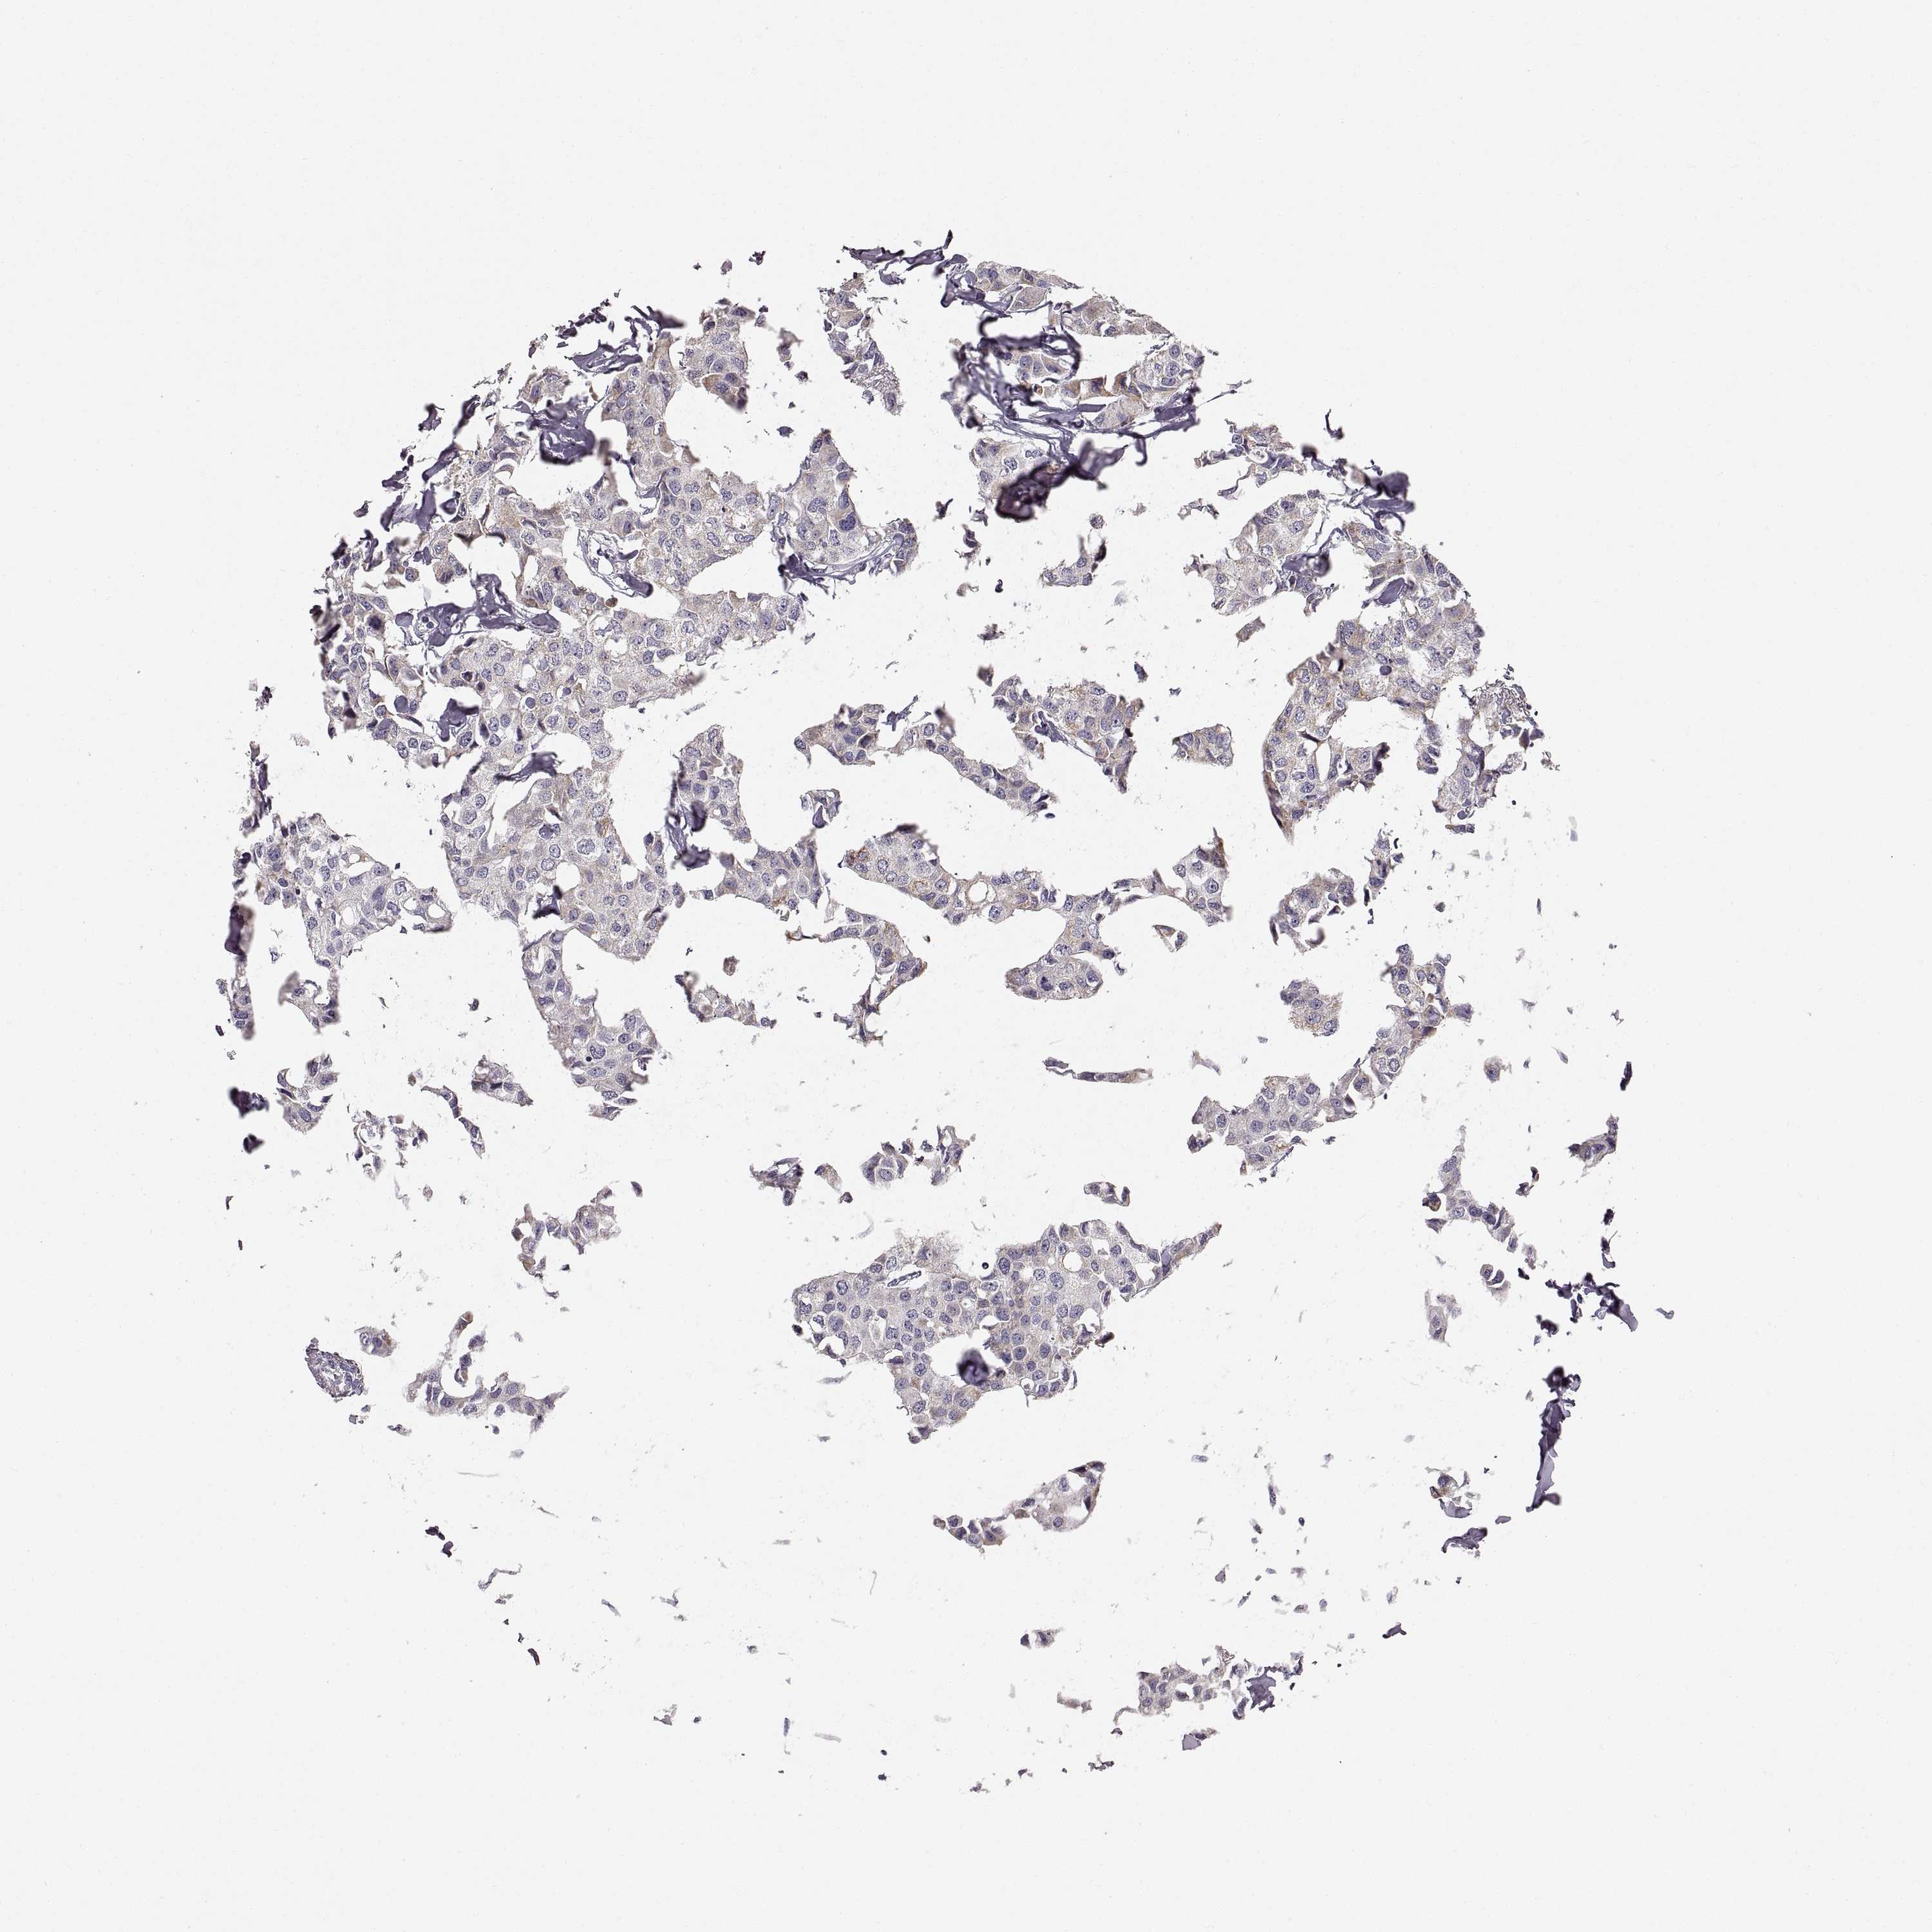

CANCER BREAST CANCER Show tissue menu

BRCA TCGA BRCA VALIDATION PROTEIN EXPRESSION